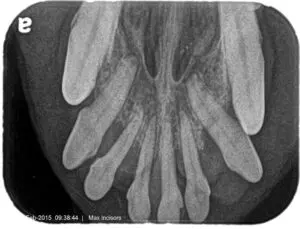

The most common teeth we see that require extraction are the mandibular and maxillary incisors, followed by the maxillary premolars. This is anecdotal, although I have been practicing dentistry since the advent of running water and flushable toilets! The reason these teeth are involved is that they (especially the incisors) are overly crowded, while also not being used to chew. Incisors are meant to be used to grab things, not chew. The incisive bone associated with these teeth is thin and not as dense as the bone that lies behind the canines.

Advanced bone loss on the maxillary incisors requiring oral surgery